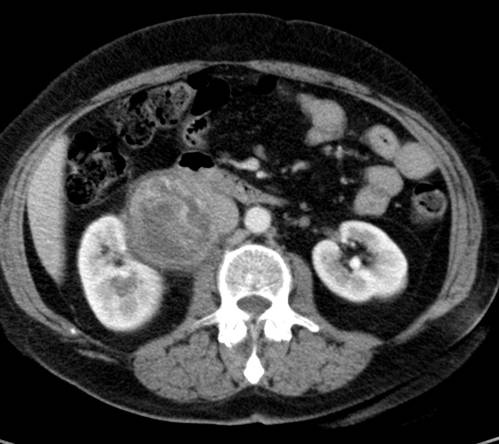

Die nachfolgenden Abbildungen zeigen die prätherapeutische CT-gestützte Biopsiegewinnung (Stanzbiopsie) bei einem pleomorphen Liposarkom im rechten Unterbauch.

Quelle: Klinik und Poliklinik für Diagnostische und Interventionelle Radiologie, Universitätsklinikum Leipzig